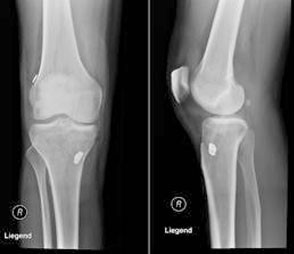

Die Patienten beschreiben, einen Riss verspürt zu haben, teilweise sogar mit einem Geräusch verbunden. Der Erguss im Gelenk und die einhergehenden Schmerzen führen dann zur Konsultation eines Arztes. Ziel ist es zunächst, das Ausmass der Knieverletzung abzuschätzen und die richtigen weiteren Schritte einzuleiten. Unfallmechanismus, Beschwerden und der klinische Befund sind oft recht typisch. Neben der standardmässig durchgeführten Röntgenbildgebung zum Ausschluss einer knöchernen Verletzung, kommt die Magnetresonanztomographie (MRT) zur Anwendung. Diese Untersuchung besitzt eine hohe Sensitivität von 90%, um eine Ruptur des VKB erkennen zu können. Die Frage, ob eine Ruptur des VKB operativ zu versorgen ist, erweist sich nicht als so einfach und hängt von verschiedenen Faktoren ab. Eine Kernfrage ist, ob ein Instabilitätsgefühl bei den Patienten vorliegt. Die Instabilität hat zur Folge, dass Knorpel- und Meniskusschäden durch vermehrte Scherkräfte auftreten können. Mit der Operation mit Restabilisierung des Kniegelenks wird dem begegnet. Ziel der Operation ist es, dem Patienten ein annährend gleiches Aktivitätsniveau wie vor dem Unfall zu ermöglichen.